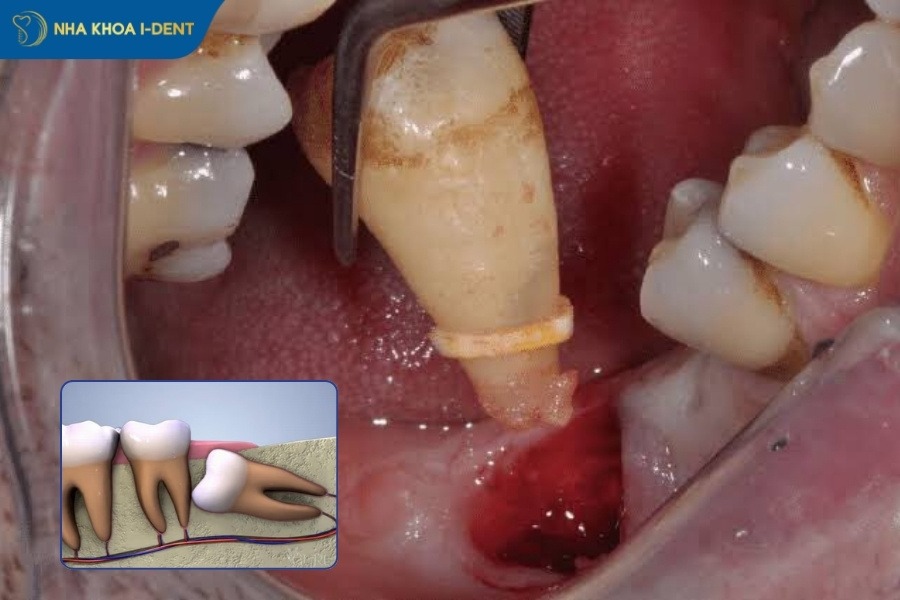

Răng khôn mọc lệch là tình trạng răng số 8 nghiêng vào răng số 7 hoặc đâm vào lợi. Việc không nhổ răng sớm có thể gây sâu răng số 7, viêm nướu và đau nhức kéo dài.

Răng khôn mọc ngầm là tình trạng răng nằm hoàn toàn hoặc chỉ nằm một phần tỏng xương hàm và không nhìn thấy bằng mắt thước. Đây là trường hợp nhổ răng khôn phức tạp và có chi phí cao nhất.